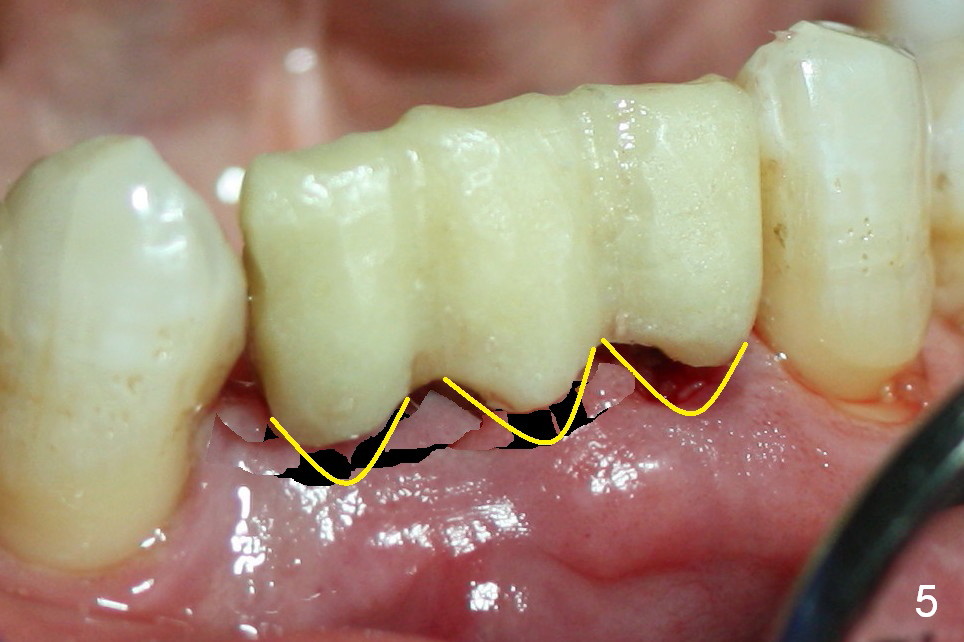

One of the functions of an immediate provisional is to maintain and create the valleys and peaks of the gingival morphology (Fig.4-6). When the wound heals initially, the provisional should be modified (Fig.5 yellow curves) to push the gingiva aside (Fig.6 arrows) to create oval pontic and papillae (Fig.5).